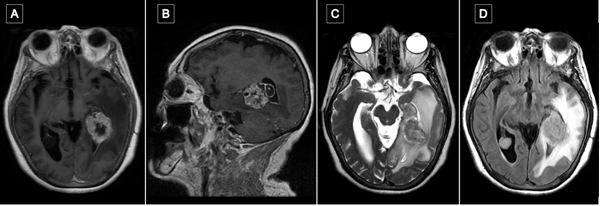

La resonancia magnética (RM) de encéfalo con gadolinio evidenció una lesión expansiva heterogénea, con áreas centrales de aspecto quístico y degeneración necrótica, localizada en la topografía temporomesial izquierda de aproximadamente 28 × 27 mm en plano axial y 29 × 26 mm en plano coronal, con realce heterogéneo tras la administración de contraste endovenoso. En secuencia de susceptibilidad magnética presentaba signos de restos de hemosiderina y/o microcalcificaciones. En el asta occipital y el atrio ipsilateral del ventrículo lateral, se evidenciaron formaciones quísticas con refuerzo periférico. La lesión descripta presentaba edema perilesional que comprometía el lóbulo temporal izquierdo y la región parietoccipital ipsilateral. Además, se observó dilatación del tercer ventrículo y ventrículo lateral homolateral. Las cisternas perimesencefálicas se encontraban libres, y las estructuras de la línea media, centradas. Las imágenes obtenidas eran sugestivas de una lesión de origen glial de alto grado (Figura 1). Se complementó con tractografía en la que se observó una disminución de la fracción de anisotropía a nivel del septum sagital con disrupción de las fibras de los tractos arcuato, frontooccipital inferior y longitudinal inferior izquierdo (Figura 2).

Figura 1. RM preoperatoria con contraste endovenoso. A y B) RM de encéfalo, cortes axial y sagital, respectivamente, en secuencia T1 contrastada, que evidencia lesión expansiva con realce heterogéneo localizada en topografía temporomesial izquierda. C) Corte axial en secuencia T2, se muestra heterogeneidad de la lesión con áreas centrales de aspecto quístico y degeneración necrótica. D) Corte axial en secuencia FLAIR que evidencia edema perilesional que compromete lóbulo temporal izquierdo y región parietooccipital ipsilateral.

Transcurrido un mes de la cirugía, se realizó resonancia magnética de encéfalo con gadolinio en la que se observó en la región temporomesial izquierda un área de señal líquida con signos de gliosis periférica y sutiles restos de hemosiderina, sin evidencia de lesión tumoral residual. Persistía el edema vasogénico con efecto de masa sobre el sistema ventricular ipsilateral (Figura 6).

Figura 6. Comparación de resonancias magnéticas pre y postquirúrgicas. A y B) RM prequirúrgica de encéfalo, cortes axial y sagital, respectivamente, en secuencia T1 contrastada, se evidencia lesión expansiva con realce heterogéneo localizada en topografía temporomesial izquierda. C y D) RM de encéfalo con gadolinio realizada aproximadamente un mes luego de la intervención quirúrgica. Cortes axial y sagital, respectivamente, en secuencia T1 contrastada en la que se evidencia en región temporomesial izquierda un área de señal líquida con signos de gliosis periférica, sin evidencia de lesión tumoral residual.